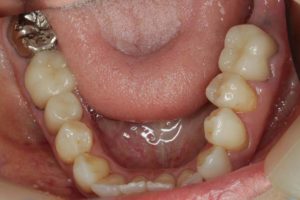

- 術前

- 術後

長い間お疲れさまでした。この方は、前歯に審美的なインプラントを入れるため、抜歯後4ヶ月待ち、仮歯で歯肉が成熟するのを数が月待っていたりした為に、完成まで時間がかかってしまいました。

虫歯治療などは短期間で終えることができるのですが、歯ぐきをいじり出すとどうしても治癒期間が必要となり長くなってしまいます。それもこれも奇麗な仕上がりのために欠くことのできないものです。何卒ご容赦を!